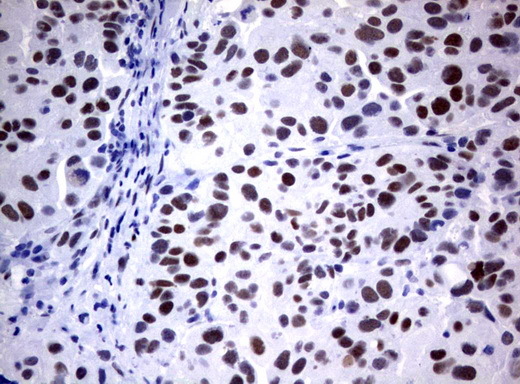

- Main image

- Experimental details

- Immunohistochemical staining of paraffin-embedded Carcinoma of Human bladder tissue using anti-FOXP1 mouse monoclonal antibody. (UM800020; heat-induced epitope retrieval by 1 mM EDTA in 10mM Tris, pH8.0, 120C for 3min)

- Validation comment

- IHC